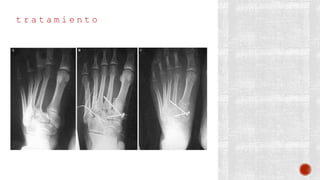

t r a t a m i e n t o

¬ Conservador: Yeso corto durante 2 a

4 semanas

¬ Quirúrgico:

- Primero y quinto metatarsianos:

Reducción abierta y fijación interna

crucial